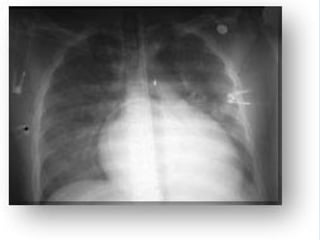

Rx Tórax